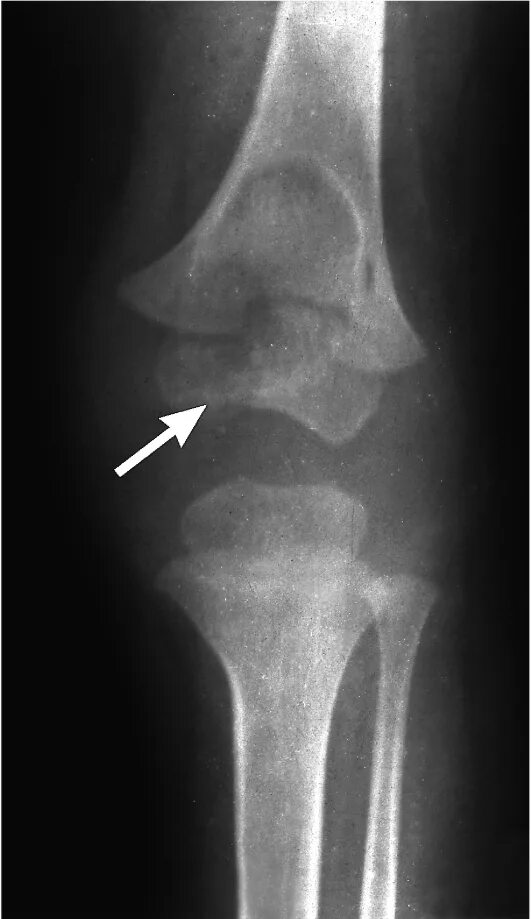

Туберкулез суставов симптомы